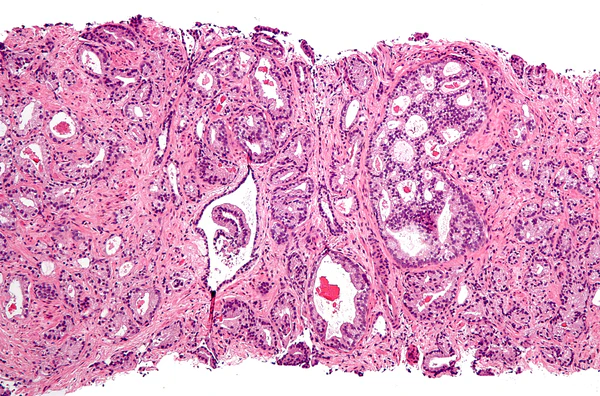

Разнообразные мутации (как правило, миссенс-мутации[14]) андрогенового рецептора, делающие невозможным внутриклеточную передачу сигнала через AR при связывании с тестостероном, приводят к развитию состояния, известного как синдром нечувствительности к андрогенам (AIS). У индивидуумов с AIS в ходе эмбрионального развития клетки Лейдига вырабатывают нормальное количество тестостерона, однако производные вольфова протока, дающие начало элементам мужской половой системы, остаются недоразвитыми. Мюллеровы протоки разрушаются под действием антимюллерова гормона, выделяемого клетками Сертоли. Семенники располагаются в брюшной или паховой области и в постпубертантный период характеризуются недоразвитыми клетками Лейдига и семенными канальцами с незрелыми клетками Сертоли и примитивными гоноцитами, развитие которых не идёт дальше стадии сперматогониев. В некоторых случаях у пациентов с полностью выраженным AIS наружные гениталии при рождении соответствуют женскому фенотипу и представлены слепо заканчивающимся вагинальным карманом, а в подростковый период начинается развитие молочных желёз. В других случаях, когда AIS выражен не в полной мере, гениталии с гипоспадией и не соответствуют ни чисто мужскому, ни женскому фенотипу. Наконец, в случае умеренно выраженного AIS пациенты характеризуются относительно нормальным мужским фенотипом и бесплодием или атрофией мышц во взрослом возрасте, обусловленной синдромом Кеннеди. В раннем детстве и постпубертатном периоде в плазме крови больных AIS отмечается уровень тестостерона, соответствующий или слегка превышающий нормальное содержание этого гормона у мужчин, а также повышенный уровень лютеинизирующего гормона. Однако в условиях полной или частичной нечувствительности к тестостерону начинают преобладать эффекты эстрогена, образующегося при ароматизации тестостерона[63].

Для развития и целостного функционирования предстательная железа нуждается в андрогенах. Врождённая дисфункция андрогенового рецептора или 5-альфа-редуктазы у мужчин приводит либо к полному отсутствию, либо лишь к минимальному развитию предстательной железы. То же самое верно и для самцов других животных. Через неделю после кастрации предстательная железа самца крысы подвергается дегенерации из-за апоптоза эпителиальных клеток (после удаления семенников уровень андрогенов недостаточен для поддержания целостности простаты). Андрогены также относятся к факторам, стимулирующим развитие рака предстательной железы. Изучение евнухоидных индивидуумов показало, что у них простата остаётся маленькой и не подвергается гипертрофии или злокачественному перерождению. Более того, в животных моделях канцерогенеза в предстательной железе необходимо наличие семенников или экзогенных андрогенов для поддержания развития опухоли. У трансгенных мышей с повышенной экспрессией AR в простате клетки эпителия простаты обновляются гораздо быстрее, чем в норме, и простатическая интраэпителиальная неоплазия (злокачественное новообразование) у таких мышей появляется значительно раньше. Хотя необходимость андрогенов для развития рака простаты не вызывает сомнений, сложно установить связь между относительным уровнем андрогенов в крови и риском развития рака простаты. Для объяснения различий в частоте возникновения и степени выраженности рака простаты были предложены расовые различия в уровне циркулирующих в крови андрогенов. Впрочем, данные по связи между уровнем андрогенов в крови и риском развития рака предстательной железы весьма противоречивы, и окончательного решения по этому вопросу нет. Возможно, противоречивость данных объясняется варьирующей активностью андрогеновых рецепторов, которая может играть исключительно важную роль в развитии рака простаты[14].